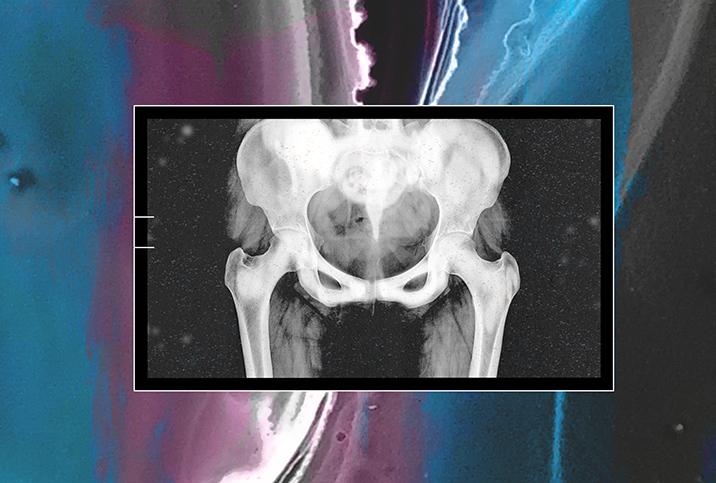

Prostate Cancer - Prevention and Risks